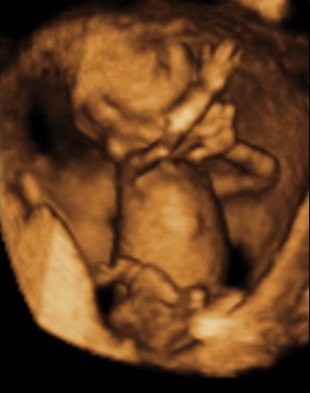

Det tror jeg på... Hehe... Sådan ser vores billeder fra kønsscanningen ihvertfald ikke ud fra uge 15 - og vi venter os en pige, så det er jo meget heldigt, at de ikke ligner hinanden